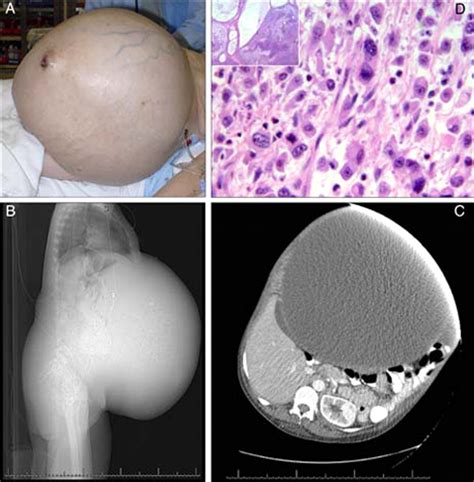

In the vast landscape of medical diagnostics and physical examinations, certain clinical indicators serve as silent, albeit significant, witnesses to underlying pathologies. Among these, the Sister Mary Joseph sign remains a quintessential example of how a simple visual observation can lead to a profound diagnostic breakthrough. This clinical finding—the presence of a palpable nodule at the umbilicus—acts as an urgent red flag, often signaling the advanced stages of an intra-abdominal or pelvic malignancy. Understanding the history, clinical presentation, and diagnostic implications of this sign is essential for medical professionals and students alike, as it represents a critical bridge between physical inspection and complex oncological staging.

The Sister Mary Joseph sign typically manifests as a firm, indurated, or ulcerated nodule at the umbilical region. While it may sometimes be misidentified as a hernia or an umbilical granuloma, its clinical significance is far more ominous. Pathophysiologically, the nodule represents metastatic spread of an internal malignancy to the umbilicus. This spread can occur through various pathways, including:

The diagnosis of a Sister Mary Joseph sign begins with a thorough physical examination. However, the discovery of the nodule is only the beginning. Clinicians must utilize a multi-modal approach to confirm the malignancy and determine the stage of the disease. A biopsy of the umbilical nodule is often the gold standard for histological confirmation.

• Histopathology: Fine-needle aspiration or excisional biopsy of the umbilical mass to characterize the cell type (e.g., adenocarcinoma).

• Imaging Studies: CT scans of the chest, abdomen, and pelvis are standard to screen for the primary lesion and evidence of distant metastasis.

• sister mary joseph nodule photos